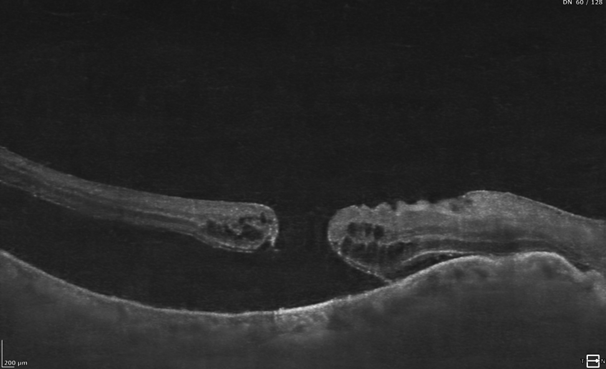

The retina is a paper-thin layer of light-sensitive tissue that lines the back of the eye. It converts incoming light into electrical signals, which travel to the brain as visual images. Retinal detachment occurs when this layer peels away from the underlying retinal pigment epithelium (RPE), disrupting the blood supply and causing the retinal cells to begin dying.

Advanced Surgical Equipment

Our operation theatre is equipped with state-of-the-art vitrectomy systems, wide-angle viewing, and high-resolution diagnostic imaging.